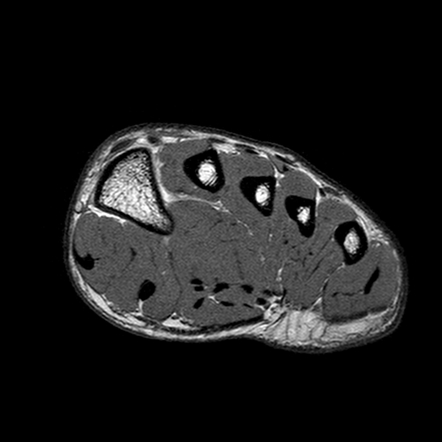

MRI - FOOT

mri atlas

MRI - FOOT

mri

MRI - FOOT

mri